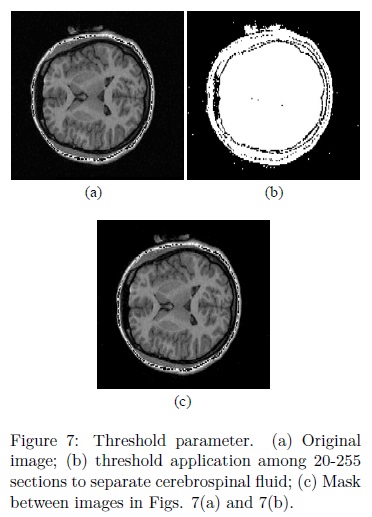

ii. The parameter Th1 represents a threshold used to eliminate cerebrospinal fluid with the purpose of disconnecting several regions between the brain and skull. According to the results presented in 20, the cerebrospinal fluid is eliminated with threshold values among 20-255 sections. Fig. 7 illustrates this situation. Original image is located in Fig. 7(a), whilst the threshold among 20-255 sections is presented in Fig. 7(b). Notice that, several components among the brain and the skull have been merged with the background, while the remaining regions are maintained unchanged. In Fig. 7(c) it is presented a mask between the original image (7(a)) and the image in Fig. 7(b). The image in Fig. 7(c) is convenient during the processing because when the leveling transformation reaches the regions where cerebrospinal fluid was located (dark regions); the propagation of the marker will be slower, obtaining in this way almost the separated brain with the leveling transformation.